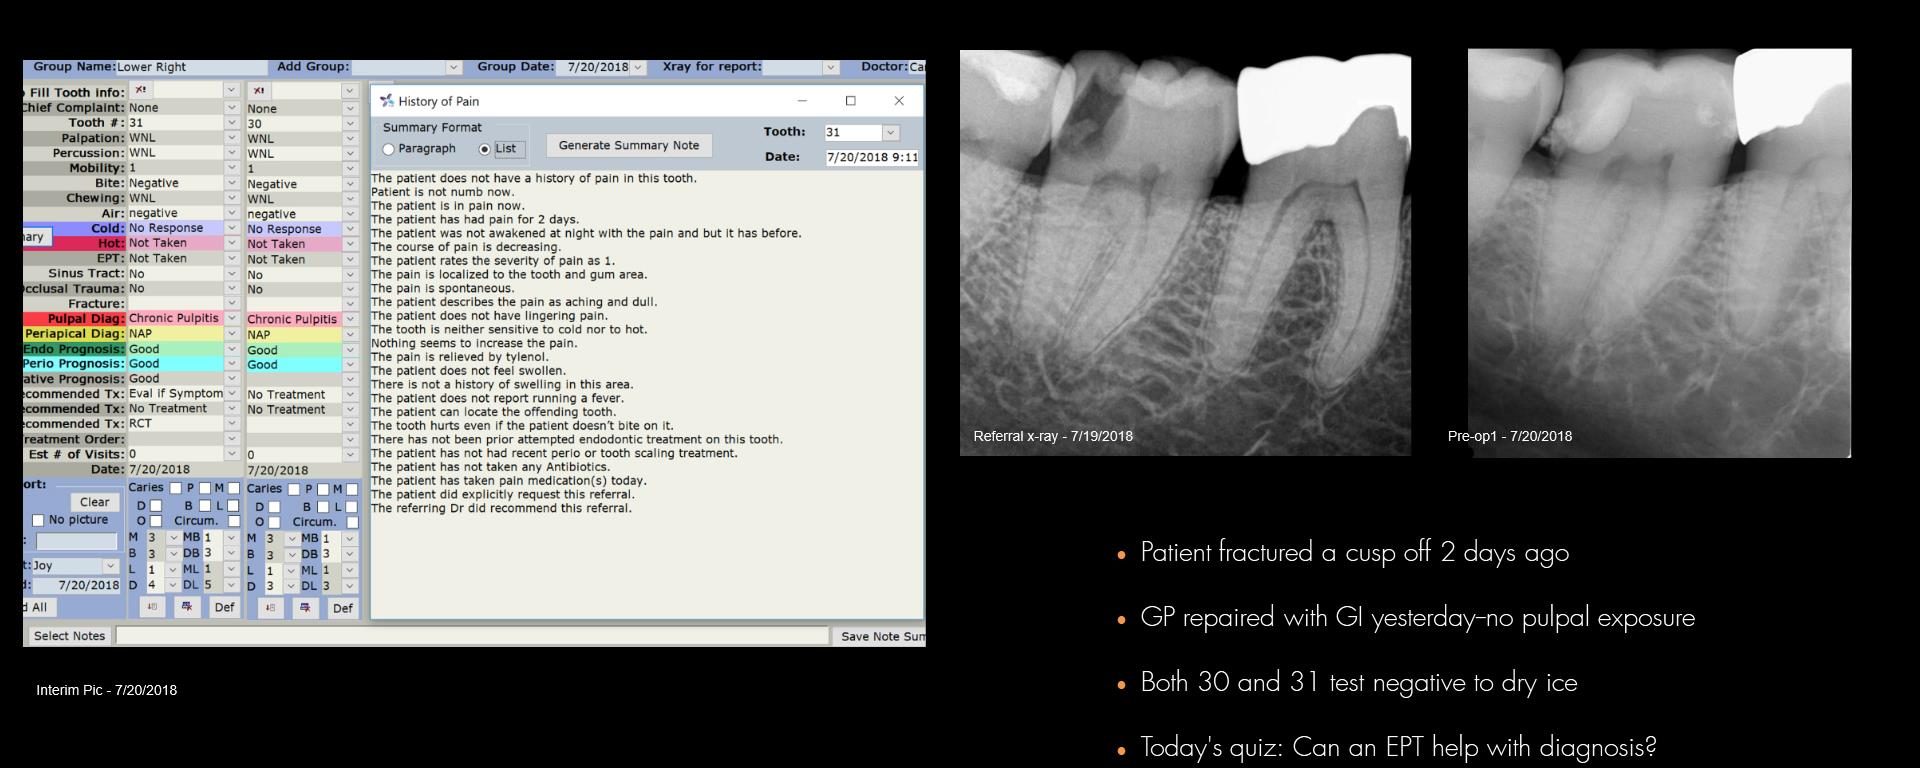

For those who think an EPT helps

July 20, 2018 2 comments

So….EPT mavens….what other tests do you run to help with the decision-making? gbc